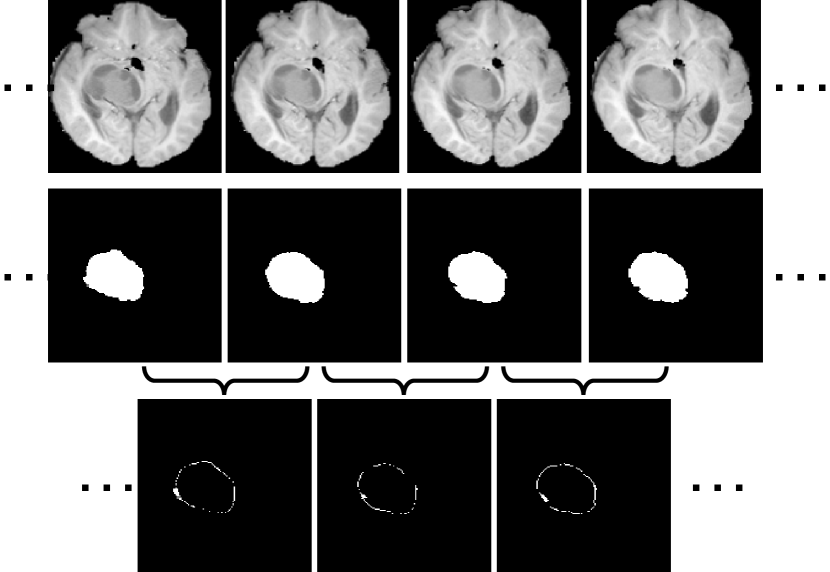

However, it is difficult to capture the inter-slice context information in volumetric images with complex anatomical structures. Take a brain tumor in a magnetic resonance (MR) sequence for example. In Fig. 1, the first row shows four adjacent slices sampled from the sequence in which there is a brain tumor, the second row gives the ground truth tumor region in each slice, and the voxel-wise difference of the tumor region between any two adjacent slices, including extending outward regions or contracting inward regions, is displayed in the third row. We define such difference as the inter-slice context residual, which appears on or near the tumor surface and contains the essential and intriguing morphological information of the tumor, since we can use it, together with the tumor region in any slice, to reconstruct the shape of the 3D tumor. Intuitively, exploring the inter-slice context residual in a segmentation process must be beneficial to improving the accuracy. Unfortunately, since the tumor regions in two adjacent slices have the similar shape and size, the inter-slice context residual is usually tiny, and hence has never been characterized directly.

Each object in a 3D medical image, such as an organ or a tumor, gradually changes cross-sectional areas on 2D slices. As highlighted by those white pixels in Fig. 3(a), the context residual indicates the discrepancy between the cross-sectional areas on two adjacent slices, which is usually tiny. We suspect that such discrepancy can also be found in the feature maps of adjacent slices produced the segmentation decoder. To verify this, we visualize the channel-wise average of the feature maps of two adjacent slices and their difference in Fig. 3(b)). It shows that those two average feature maps look similar in most regions and the dissimilarity only appear in a small fraction of the slice, which is similar to the pattern of context residual shown in Fig. 3(a). Therefore, we design a context residual module to capture the context residual based on the feature maps produced the segmentation decoder.